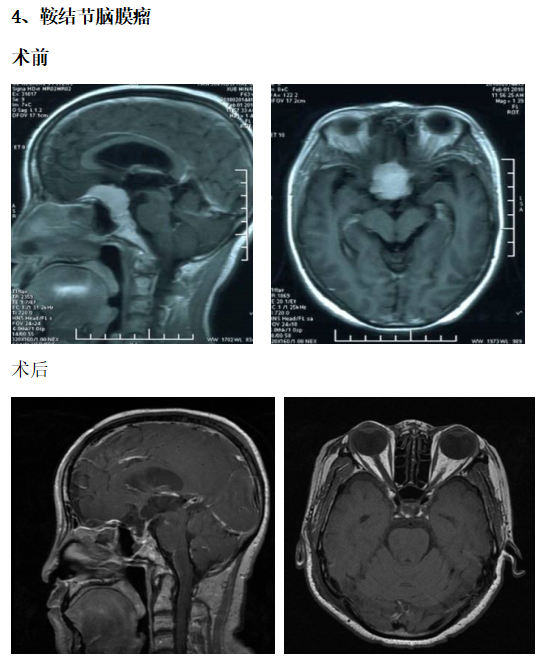

典型病例介绍